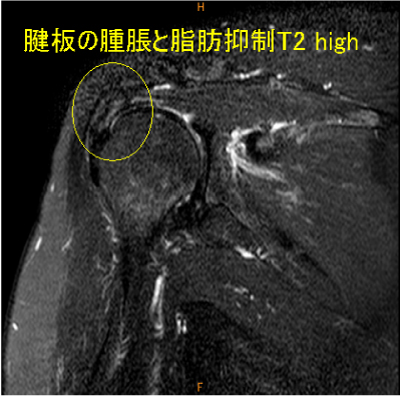

MRI所見

腱板疎部損傷症例である。

この疾患の存在を想定して読影していないと見逃す。

全層断裂が無く、肩甲下滑液包の発達が不良の症例に認める。

MRIでも特徴的な所見を呈する。おそらく見落としが多いと想像する。

拘縮性腱板疎部損傷, 棘上下筋腱 腫脹著明